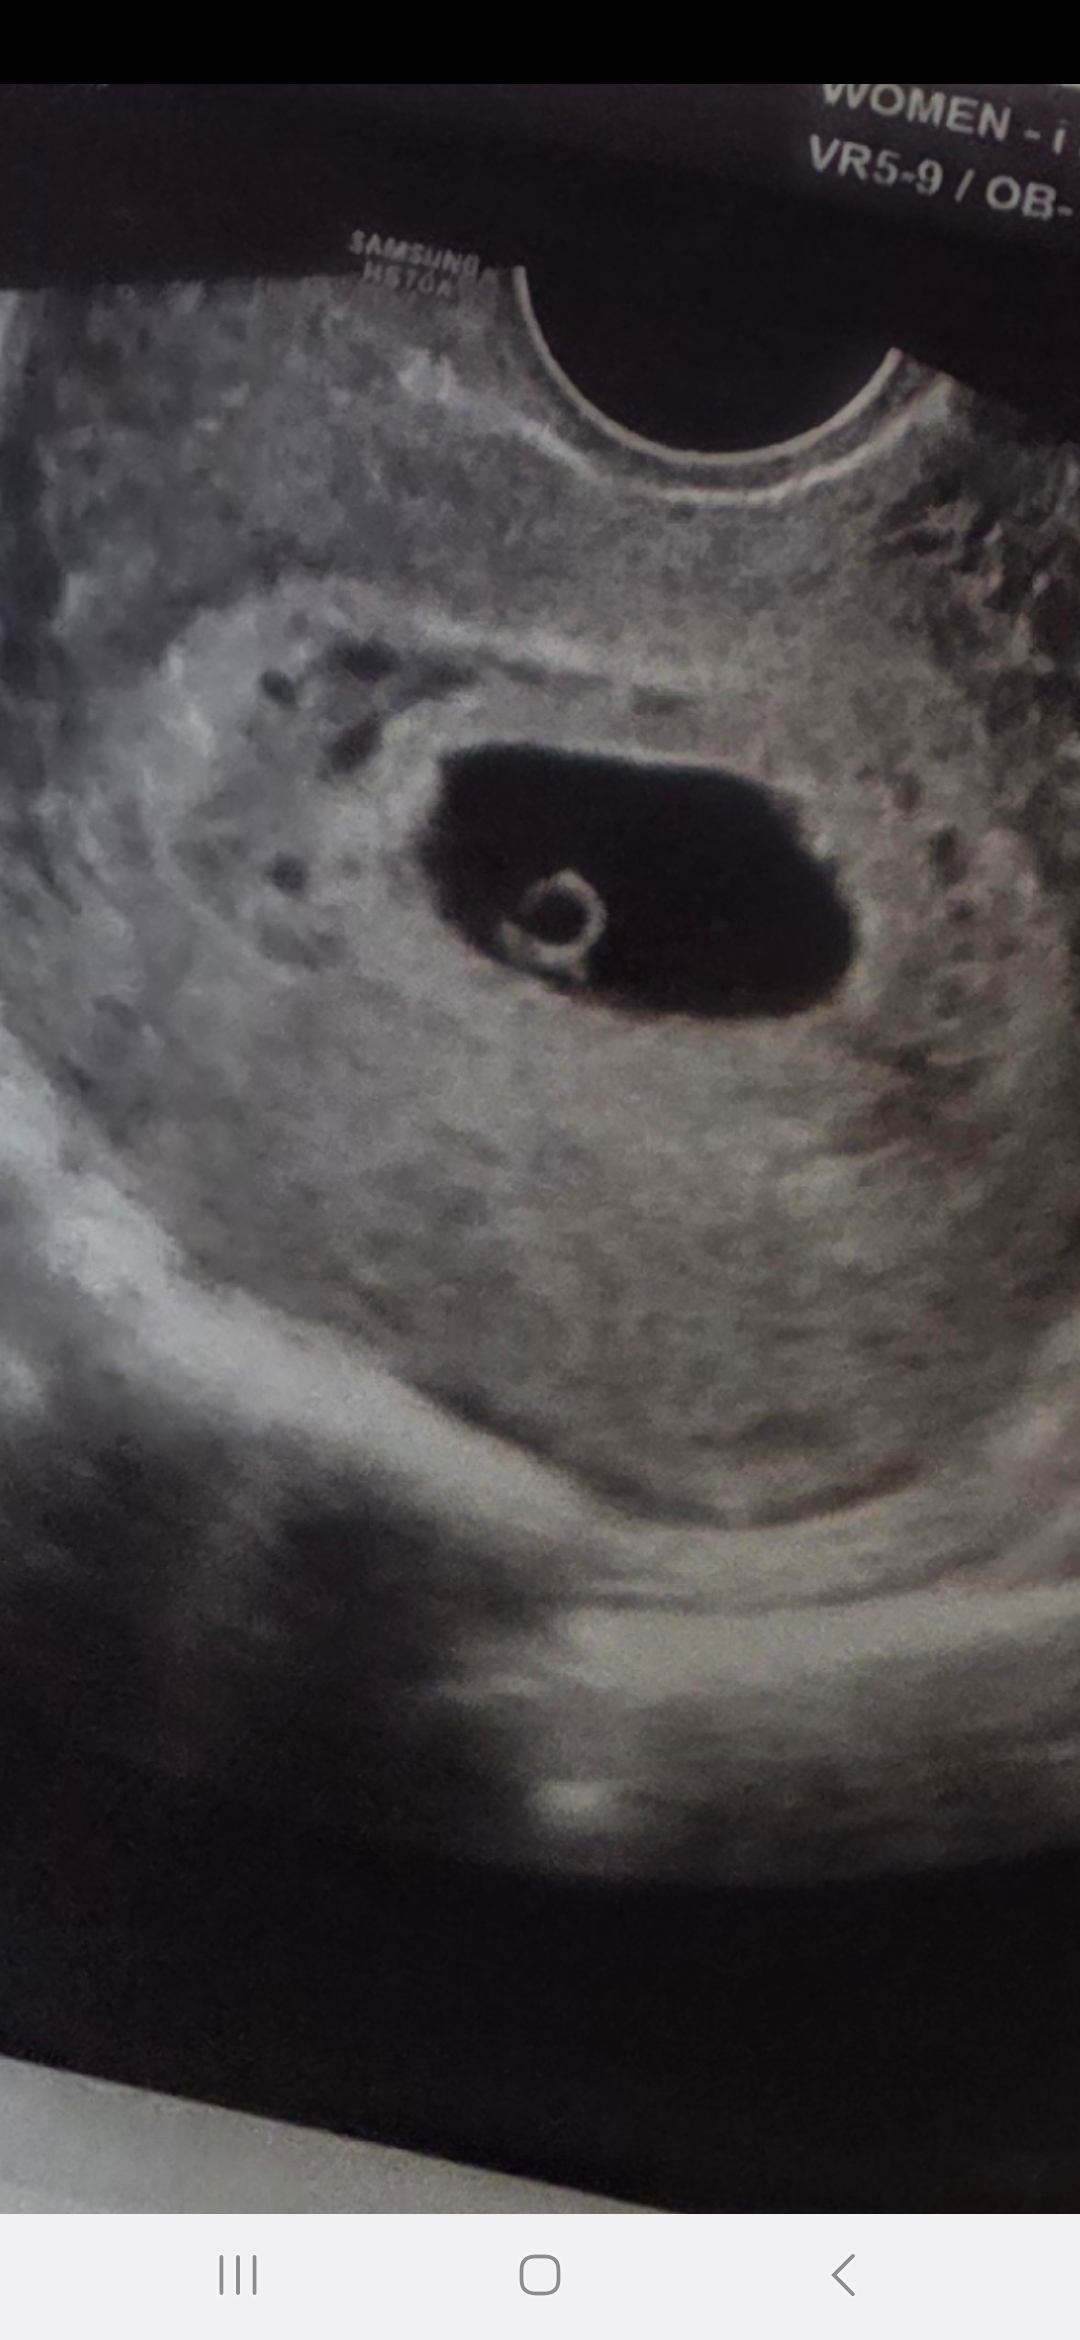

5주차 4일(지난주)이라고 하는데 생리예정일에 비해 좀 작다고 하네요 ㅜㅜ 지난번 처럼 그럴 가능성도 있고 유산 후 생리는 주수가 잘 안맞을 수 있어서 배란이 불규칙할 수 도 있다 하는데... 이번주 병원 와서 심장 뛰는지 봐야 확실하다 하시더라구요. 정말 하루가 더디게 가는 요즘입니다. 별일 없겠죠 ㅠㅠㅠㅠㅠ 답답하고 걱정만 하게되서 글 남겨봅니다. 괜히 배가 아픈거 같고 사소한 증상에도 예민해지네요....😭